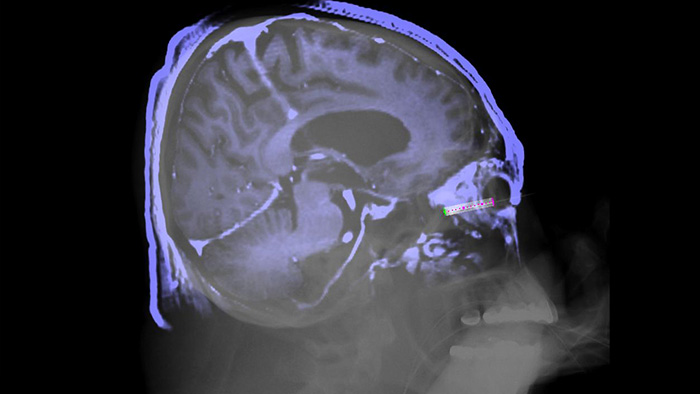

XperGuide 3D image needle guidance

XperGuide offers live 3D image needle guidance, letting you bring percutaneous needle procedures into the Hybrid OR. It overlays live fluoroscopy and 3D soft tissue imaging data from previously acquired CT or MR scans or Philips XperCT, providing information on the needle path and target.